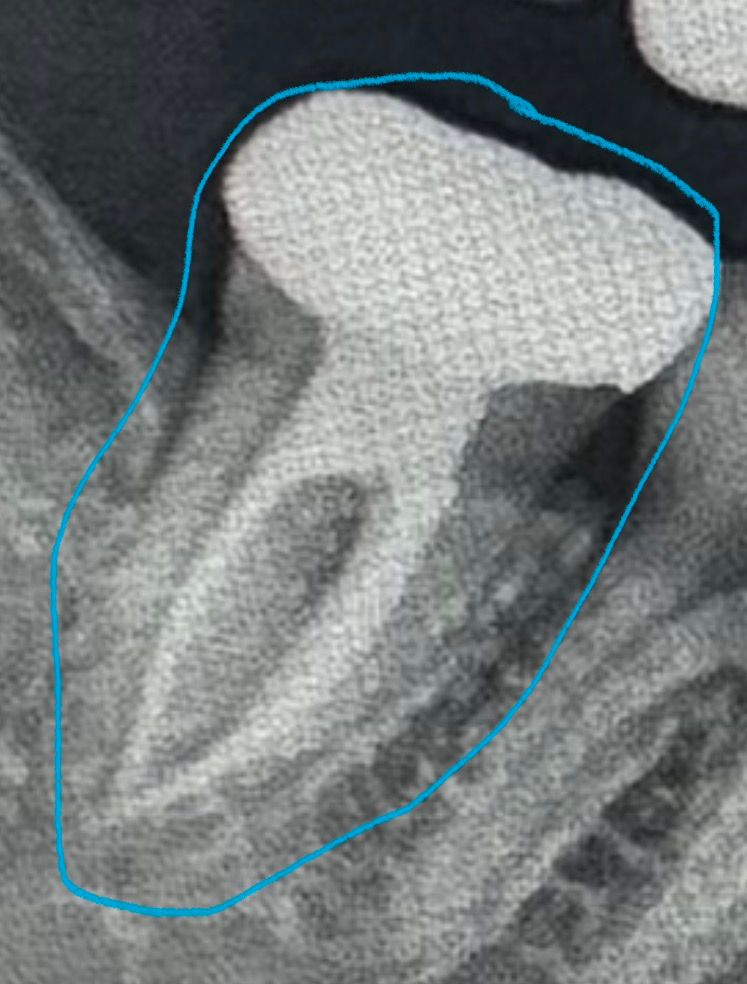

몇년전에 신경치료하고 크라운(금)씌운 어금니가

뜨겁고 차가운거에 반응은 없고 3-4일전부터

음식을 씹을때

약간의 통증이 있습니다

오늘 치과를 방문했는데 오늘 아침부턴 또 통증이 없었어요 며칠전에는 아팠는데 지금은 안아프다고 일단 검사 받으러왔다 말씀드리니 엑스레이 찍고 봐주셨는데 신경치료도 매우 잘되어있고, 염증도없고 치석없이 이가 전부 관리 잘되어있다고 하셔서 스켈링만 받고 나왔는데

신경치료는 잘된 치아 같습니다. 아마 잇몸에 염증이 생겨서 그럴수도 있으니 치과에 가셔서 잇몸치료를 받아보세요.

이미 신경치료가 잘 되어 있어 보여 다른 치료가 마땅히 없습니다. 계속 불편하면 발치가능성도 있습니다.

놓친 신경관이 있어서 그럴 수도 있고요 c형 형태의 고난이도 근관이기에 놓친 숨은 신경관이 있을 수도 있습니다 아니면 치아에 금이가서 그럴 수도 있습니다